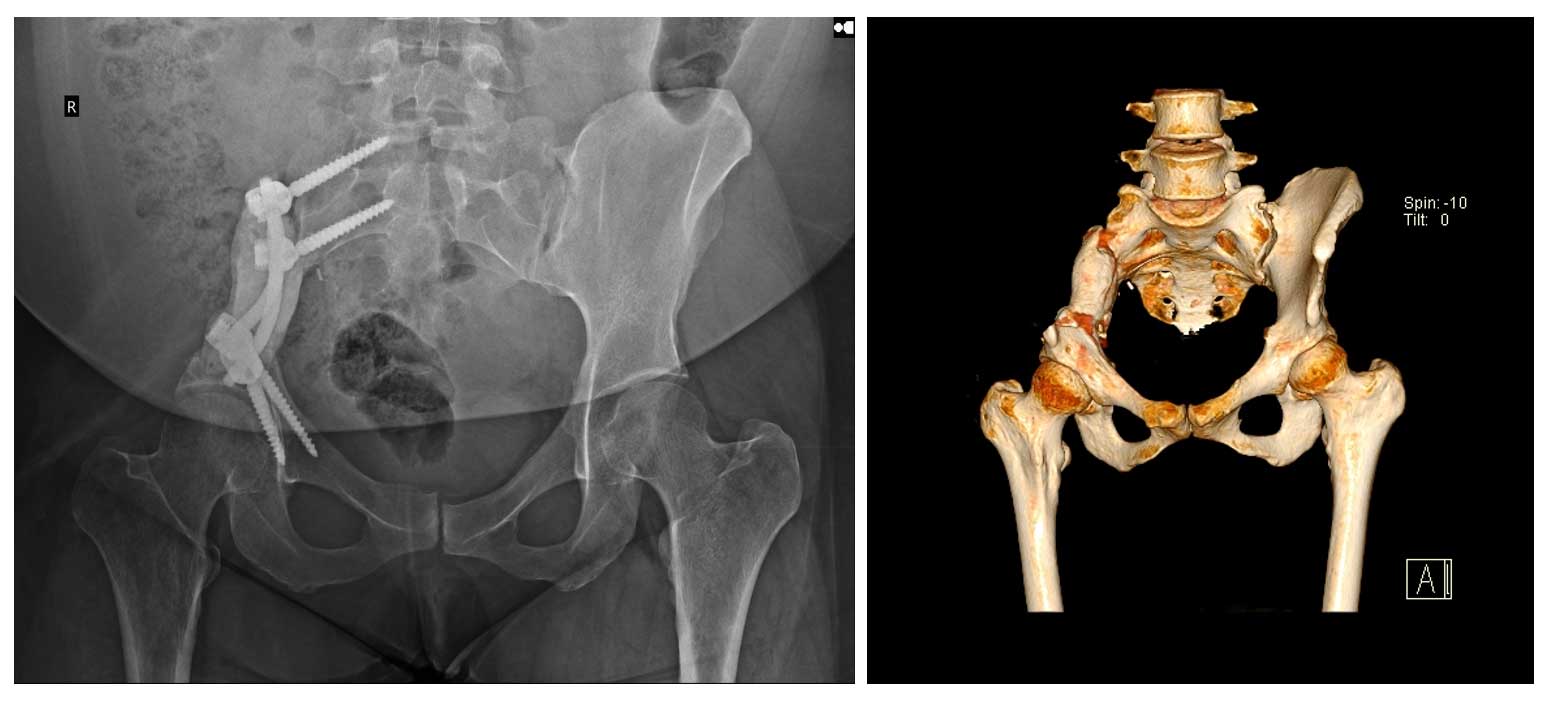

Ameliyat Sonrası: Röntgen ve tomografide internal hemipelvektomi sonrası rekonstrüksiyon işlemi görülmekte.